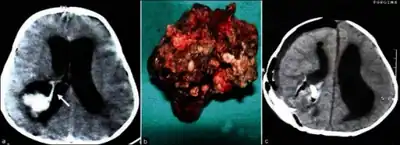

Micrograph of a choroid plexus papilloma. H&E stain. -

Plexuspapillom Detail -

Plexuspapillom Overview